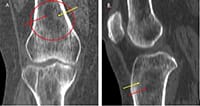

Tomografia computadorizada (TC) nos planos coronal (A) e sagital (B) evidenciando lesão heterogênea com centro radiolucente (setas vermelhas) e halo esclerótico (seta amarela).